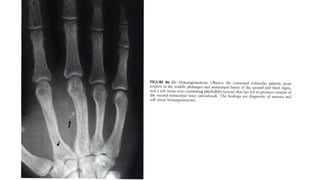

Subcutaneous nodules. Observe the prominent

soft tissue nodules in the second and third

digits, with acro-osteolysis of the terminal

tufts.

 Highly probable sarcoid arthritis includes the typical features of the

trabecular pattern, osteolysis, cyst formation, and punched-out lesions

 Highly probablesarcoid arthritis includes the typical features of the trabecular pattern, osteolysis, cyst formation, and punched-out lesions